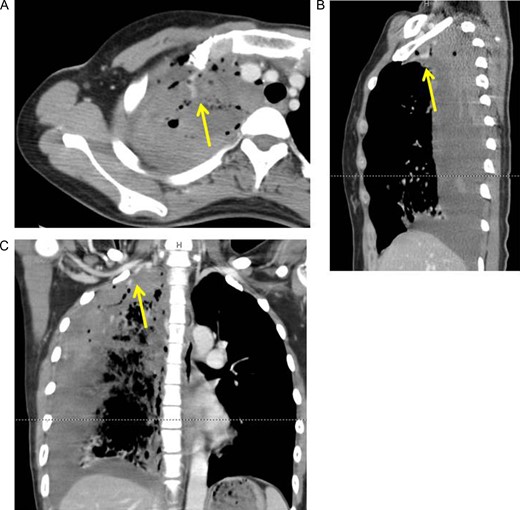

However, 2 h after the drainage, tachypnea and shock vitals (blood pressure: 78/60 mmHg, heart rate: 120/min) were identified. Repeated chest X-ray revealed an increase in the amount of right pleural fluid. The hemoglobin level of the blood from vessel decreased to 6.4 mg/dl. Contrast-enhanced CT was performed. It revealed extra-vascular signs at the top of the right pleural cavity (Fig. 2A–C).

Axial (A), sagittal (B) and coronal (C) view of contrast-enhanced computed tomography revealed extra-vascular signs (arrows) on top of the right pleural cavity.